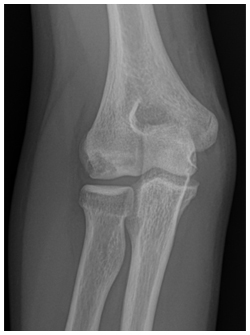

- Radiographs are used to detect the size, location and severity as well as skeletal age of the patient.

- Contralateral X-rays can help determine patients age as the affected side will have premature closure of the capitellum and radial head physes with delayed closure of the medial epicondyle and olecranon physes secondary to valgus stress overload

X-rays demonstrate a large lateral lesion within the capitellum consistent with an OCD lesion. The articular surface appears irregular

- Various classification schemes help determine severity. This includes:

- Grade I: Localized Flattening of articular cartilage

- Grade II: Nondisplaced fragmentation of the cartilage

- Grade III: Displaced or detached fragments/sclerosis or loose bodies

***Location of lesion on capitellum is important because lateral lesions tend to have inferior outcomes than central lesions

*** Throwing athletes tend to have more anterior lesions compared to gymnasts

- “Stable” lesions have been defined as those with open capitellar physis, localized flattening and radiolucency of subchondral bone with near normal elbow range of motion. Grade I is considered stable and Grade III is unstable. Grade II can be stable or unstable